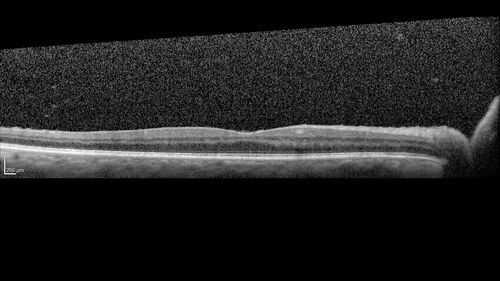

Acute retinal necrosis

67 year old female Hazy vision in the right eye for 5 days.

Medical Hx: TYPE 2 DIAB.. Hypercholesterolemia.

Systemic Meds: CRESTOR 10 MG QD. METFORMIN 500 MG QD. PROLIA Q 6 MOS. SULFA 800 MG/ TRIMETHOPRIM 160 MG TID. VALCYCLOVIR 1 GM TID. PROBIOTIC QD. CENTRUM 50+ QD. ALLERGY MED QD

VA 20/40, 20/20

IOP 19, 12

SLE: Trace AC cell OD and moderate vitreous cell OD